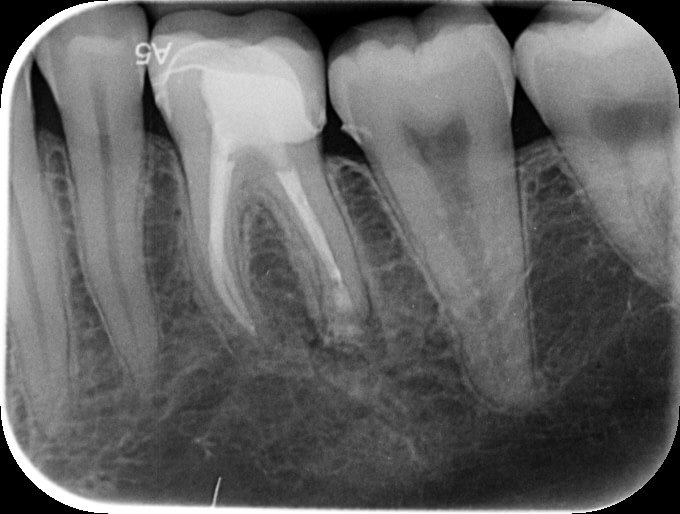

Post op PA showing completed apicectomy with retrograde MTA putty root filling and bone graft.